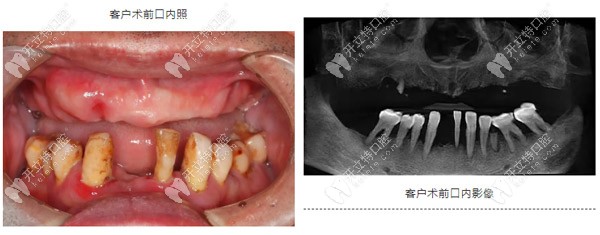

67歲,男,重度牙周炎二十多年,缺失牙十多年,一直戴活動(dòng)義齒,但因?yàn)榱x齒的固位不太好,使用不方便。

1、牙齒有重度牙周炎,造成了牙槽骨的重度流失;

2、前牙區(qū)牙槽骨寬度不夠,骨量狹窄;

3、后牙區(qū)骨高度不足,需要進(jìn)行斜型種植;

4、上頜竇腔偏斜,特別考驗(yàn)種植體的位置精準(zhǔn)度,方向需要與竇腔平行;

5、上唇豐滿度不夠,需要進(jìn)行前牙植骨

這個(gè)一個(gè)十分典型的牙周病種植病例,因?yàn)橛卸鄠€(gè)難點(diǎn),且種牙在操作過程中屬于半盲區(qū),所以十分考驗(yàn)種植醫(yī)生的技術(shù)和經(jīng)驗(yàn)。